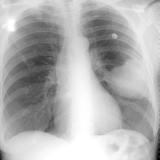

Mets

Album: Mets

Date: 02/18/2006

Size: 52 items

Views: 39060